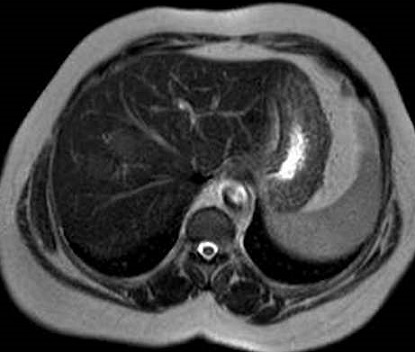

Meme cas en IRM

ponderee en T2 non perfusion intraveineuse : Aspect du

tumeur est hypersignal ( fleche blanche ) |

Image IRM ponderation T1 plus contrast

intraveineuse . En phase de veine porte c'est image

de rehaussement progessive de peripherique vers le

central |